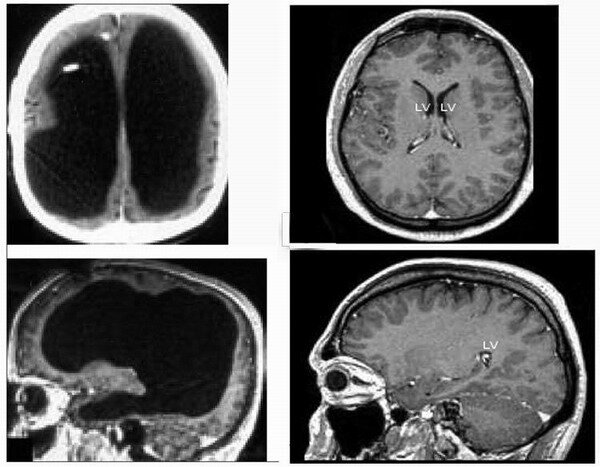

Совсем недавно, в июле 2007 года, в авторитетнейшем медицинском научном журнале «Lancet» была опубликована небольшая статья «Мозг клерка». В ней рассказывалось о поразительном случае гидроцефалии у одного 44-летнего французского государственного служащего. Однажды этот человек обратился в госпиталь Марселя с жалобами на слабость своей левой ноги, однако, когда ему сделали томографию мозга, то врачи, увидевшие снимки, были шокированы. Оказалось, что желудочки мозга этого клерка были так расширены, что занимали практически всю полость черепа. Тем не менее, хотя почти три четверти головного мозга отсутствовали, этот человек жил (да и сейчас живёт) вполне нормальной жизнью: работа, семья, дети...

Как известно, даже малейшие нарушения работы мозга могут проявляться в виде сильных психических расстройств. Так, участок поражения размером в несколько миллиметров способен, в зависимости от своего местоположения, привести к нарушениям речи, памяти, сознания, восприятия и пр. Однако наш «безмозглый» клерк из Марселя никаких особых проблем с психикой, как ни странно, не испытывал. Хотя он и был, честно говоря, несколько глуповат — его средний коэффициент интеллекта (IQ) составлял всего 75 при норме от 80 до 114. Однако некоторые виды его интеллекта были развиты лучше. Так, например, его вербальный IQ был уже равен 84, что вполне сравнимо, к примеру, с IQ президента США Дж. Буша младшего, у которого он, как говорят, равен 91. Клерк жил обычной жизнью: исправно ходил на службу, был женат и имел двоих детей. Если бы у него не возникли проблемы с ногой, то, возможно, никто бы и не узнал, что в его голове большую часть «жилой площади» занимает не мозг, а спинномозговая жидкость (ликвор).

Нечто подобное уже было описано в 1980 году в журнале «Science». Роджер Левин (Roger David Lewin) опубликовал там свою статью «Действительно ли вам нужен мозг?» (Is your brain really necessary?), в которой описал несколько случаев гидроцефалии из практики профессора педиатрии Шеффилдского университета Джона Лорбера (John Lorber, 1915–1996). В их числе и случай студента, который в середине 1960-х обратился к врачу с жалобой на незначительное недомогание. Врач отметил, что размер головы молодого человека немного превосходил норму и для более детального обследования отправил его к своему знакомому — профессору Лорберу. Сканирование показало, что всё пространство черепной коробки студента занимали желудочки, заполненные ликвором. Нервная ткань его мозга представляла лишь тонкий слой в несколько миллиметров вокруг них. Тем не менее, этот студент не страдал какими-либо отклонениями в психике (его IQ был даже несколько выше нормы и составлял 126). Он успешно учился (особенно преуспевал в математике) и даже смог с отличием окончить университет.